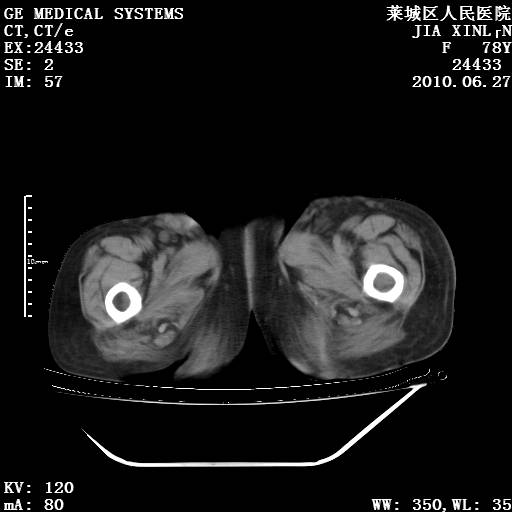

以下是引用胡宇在2010-7-2 19:11:00的发言:[br]神经纤维瘤的特点为:肿块呈多发性、数目不定,少的几个,多的可成百上千难以计数。小的如米粒,大的似拳头,甚至可达十数公斤以上。可松弛地悬挂于皮表,皱褶及松弛可致畸形明显。神经纤维瘤沿神经干的走向生长时呈念珠状,或蚯蚓块状形结节。此外神经纤维瘤皮肤可出现咖啡斑,大小不一,形如雀斑小点状,或大片状,分布与神经纤维瘤肿块的分布无关。肿瘤数目不多的患者,皮肤色素咖啡斑状沉着是纤维神经瘤的重要诊断之一。 本病多发于躯干,有时出现于四肢及面部,患者常合并许多疾病应予重视加以区别。 [br] [br] [br] [br]lyb999说 [br]